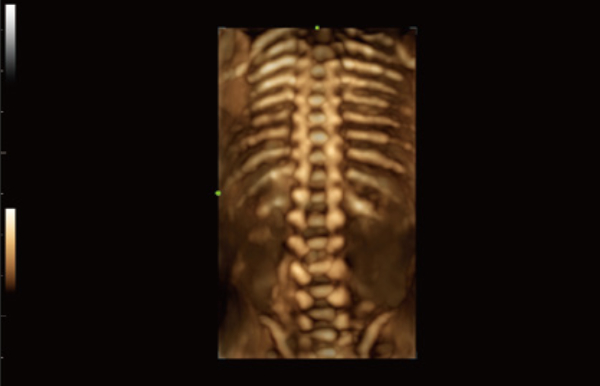

Uitgebreide?oplossingen voor beeldvorming aangestuurd door ZST?+

Het ZST+?platform is een buitengewone innovatie en revolutie in de wereld van echografie. Het transformeert echografiegegevens van conventionele bundelvorming naar kanaalgegevensverwerking. Het overwint de traditionele afweging tussen ruimtelijke resolutie, temporele resolutie en weefseluniformiteit, en levert een uitzonderlijke beeldkwaliteit voor oneindige beeldvormingsoplossingen met non-stop verbeteringen.